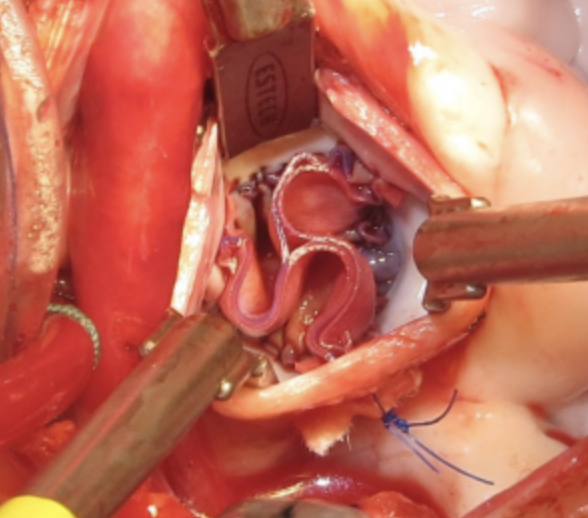

The AVNeo™ Sizer System is a single-use device used to perform an aortic valve neocuspidization required for all valve diseases, including aortic stenosis and aortic insufficiency (with or without infective endocarditis). The Sizer System allows surgeons to measure the distance between the native aortic valve commissures to determine the appropriate size of the replacement heart valve leaflets for cardiac valve reconstruction utilizing the patient’s autologous pericardium or similar.